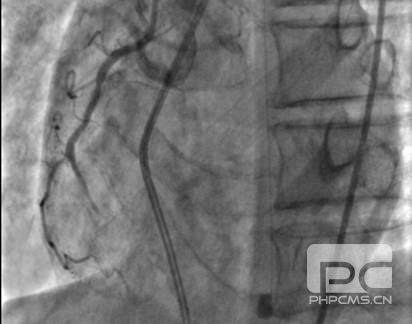

再次和家属充分沟通,告知目前行冠脉造影检查开通堵塞的血管虽然风险很高,但是是唯一可能起死回生的办法。家属充分理解后行造影。结果为前降支(LAD)近段 50-90%狭窄,LAD中段 95%狭窄,TIMI 2级血流,D1 50%狭窄,D2 50-75%狭窄,LAD远段至右冠(RCA)侧枝循环形成;回旋支(LCX)远段100%闭塞;RCA中段 25%狭窄,RCA远段100%闭塞伴血栓形成。

LCA